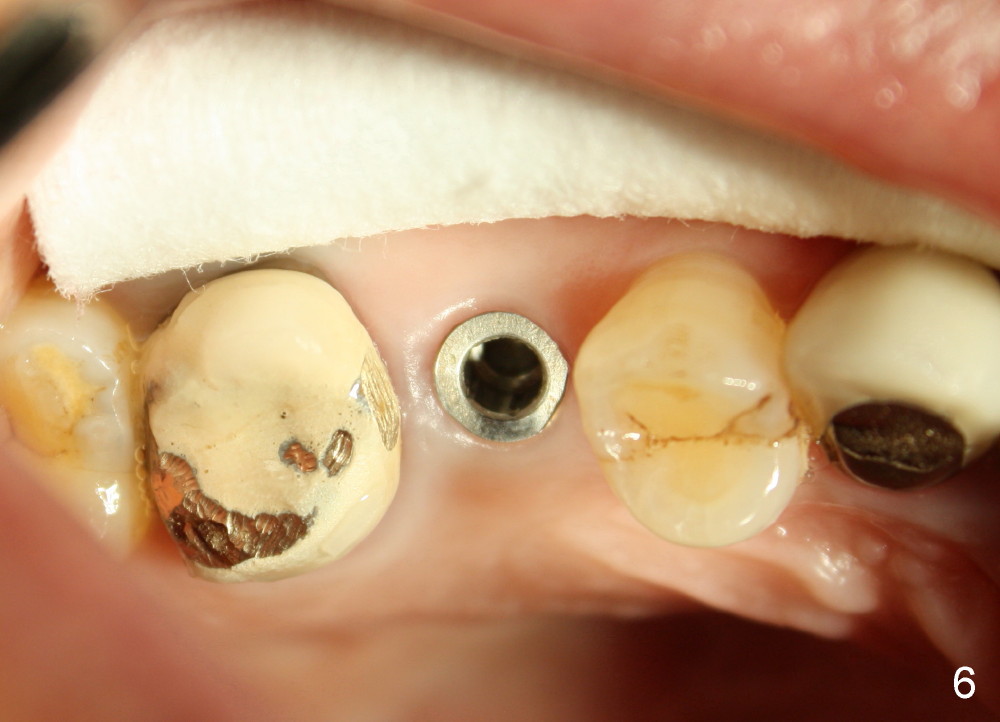

Immediate provisional is aborted due to low torque value and patient's in-cooperation (fear). A healing cuff (4.5 mm in diameter) is placed to close the buccal gap (Fig.5). The joined crowns are separated. The crown for #3 is recemented. Finally perio dressing is placed around the implant. The healing cuff is removed 6 days postop because of pressure. The patient returns for restoration 9 months postop. The gingival tissue is healthy around the implant (Fig.6). The bone density around the implant increases (Fig.7 *, compare to Fig.4).